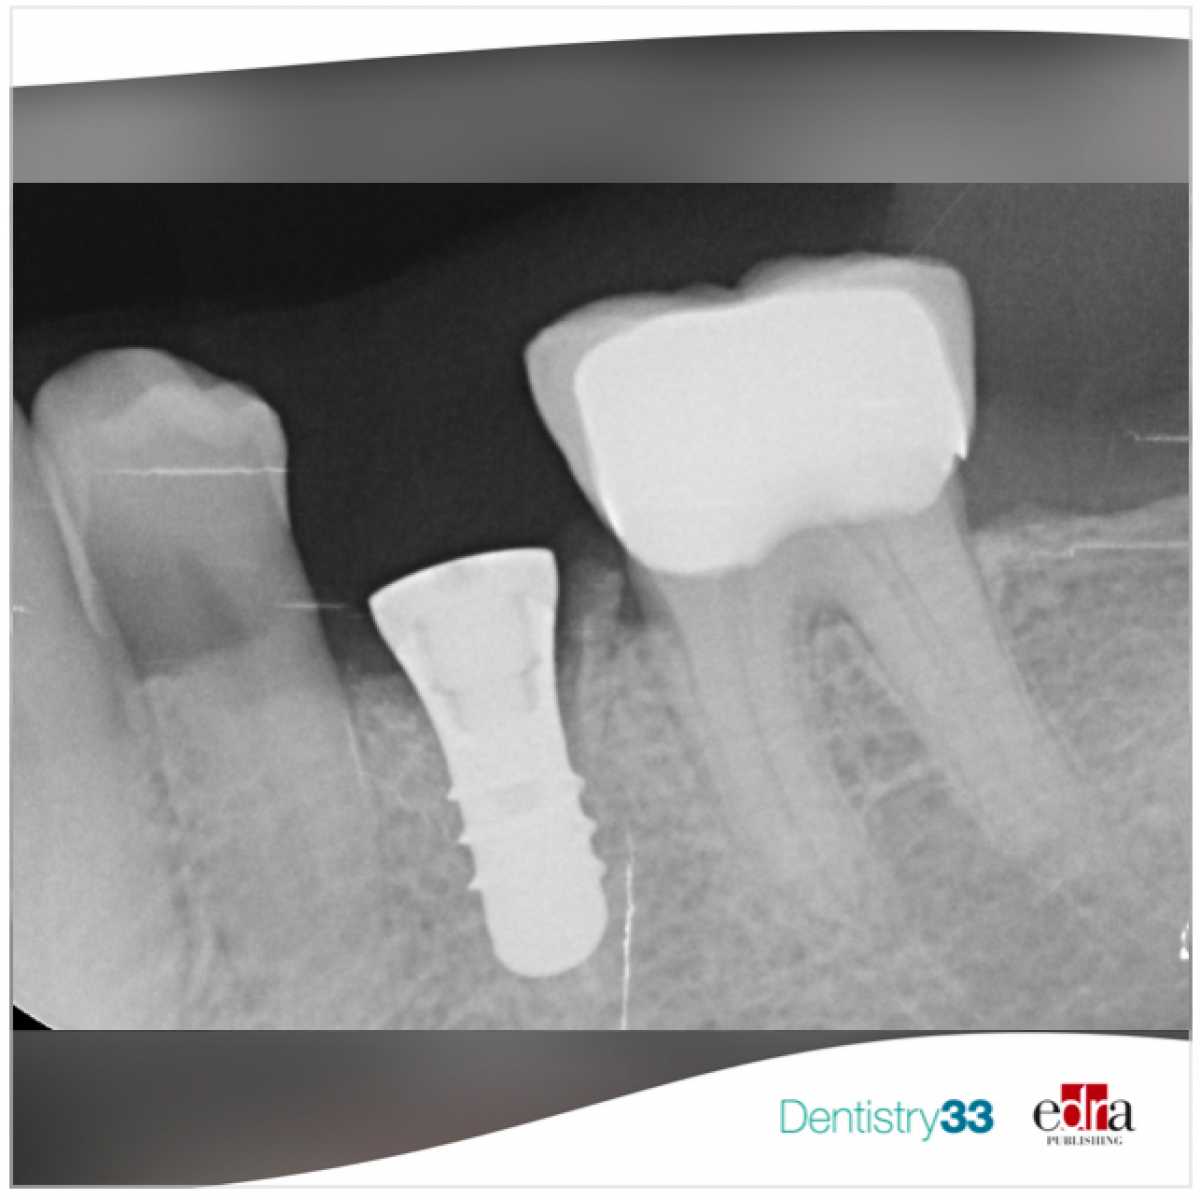

To be convincing, the dentist has the task of explaining to patients in a simple, easy to understand way and without going too far into technical details, that there are several ways to replace a missing or lost tooth, including removable and fixed prostheses. Among the fixed prostheses there can be bridge solutions on natural teeth and the implant solution, more conservative because it does not touch neighboring teeth.